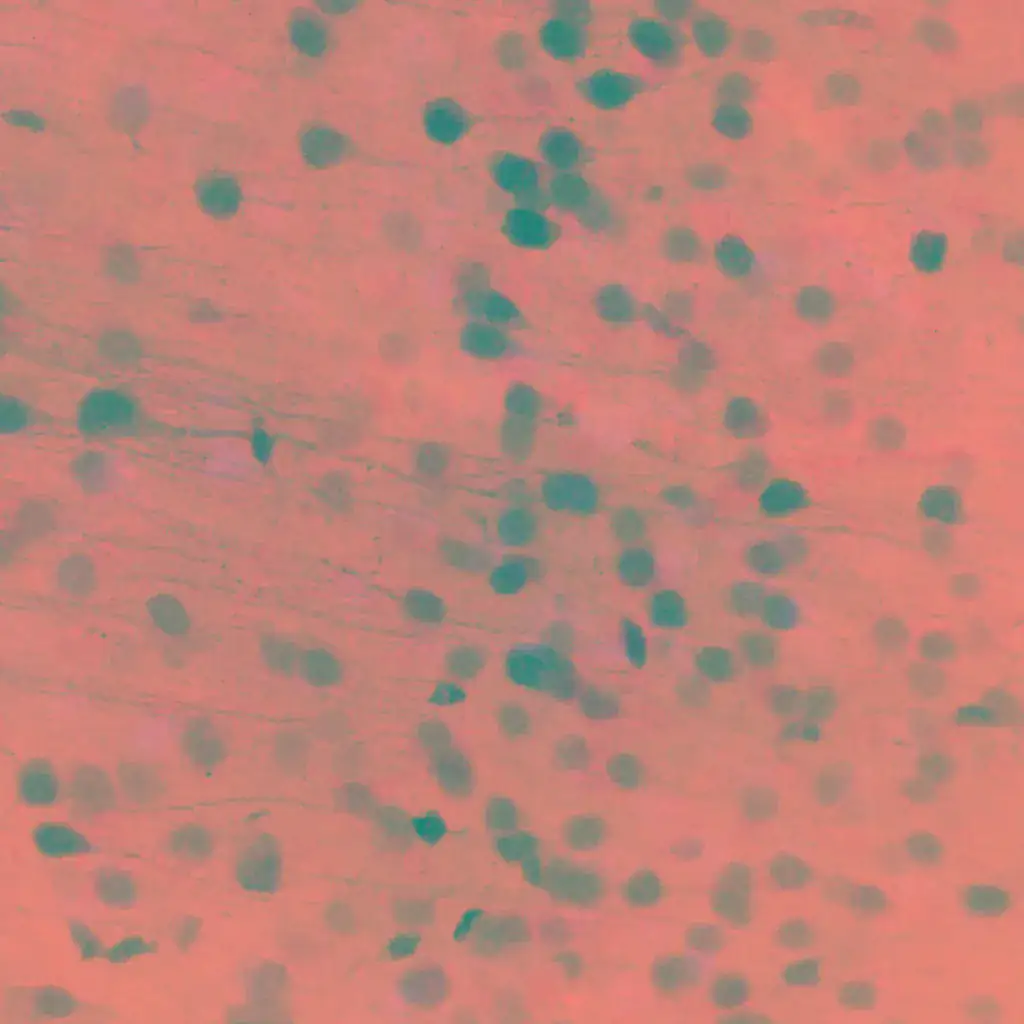

Keith Murai

McGill University

Canada